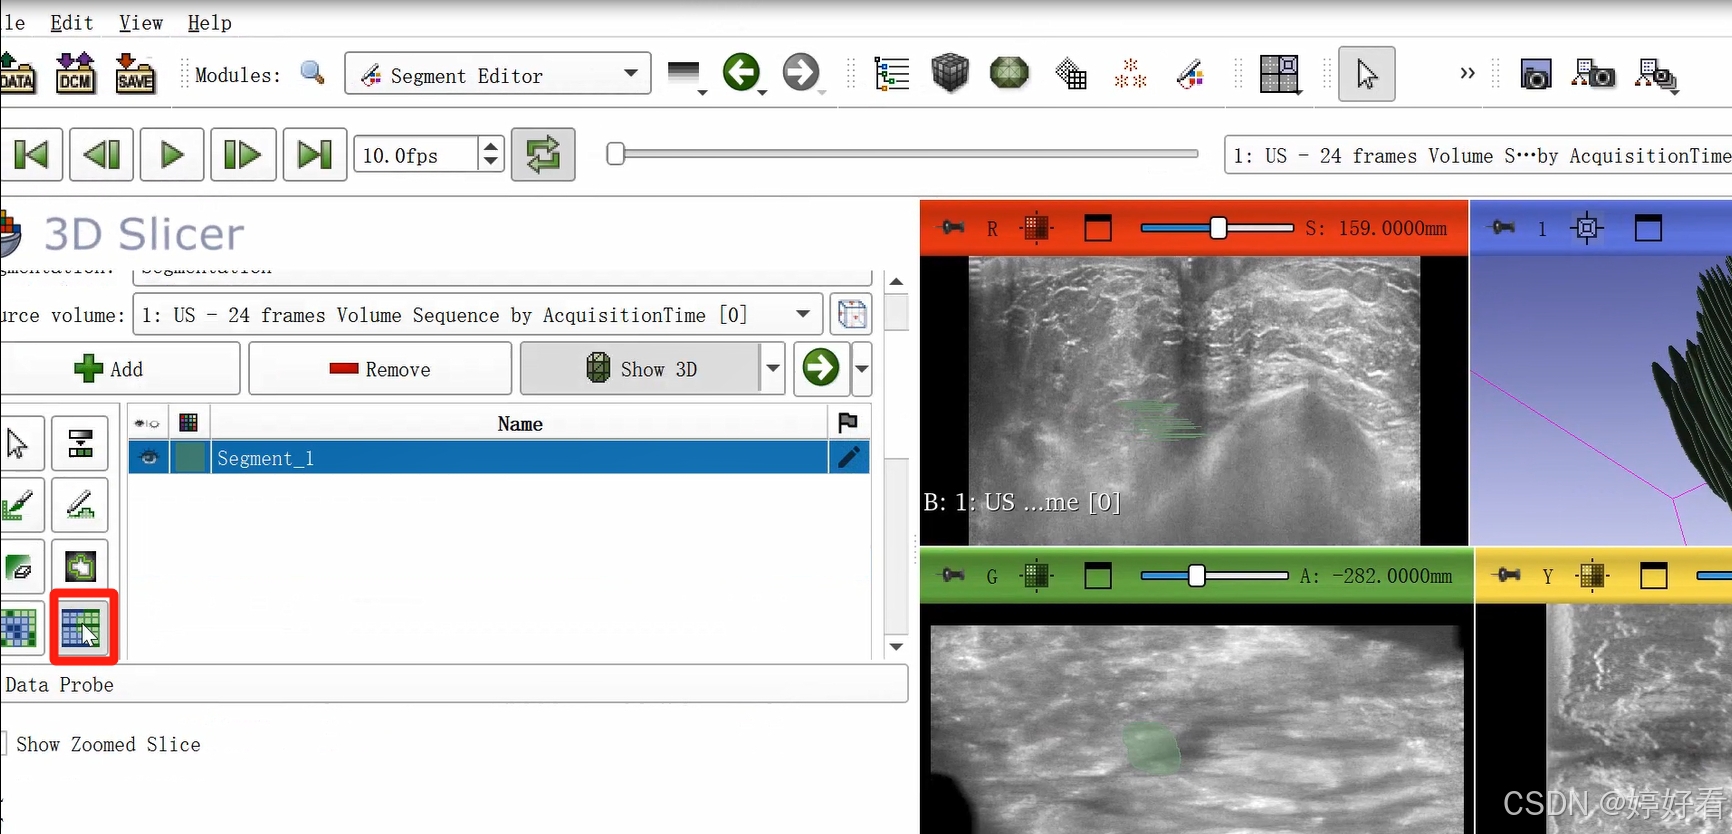

2.6 使用Fill between slices功能

上一步中完成的三维图像不是完整连续的三维图像,是一层一层的。Fill between slices这个功能可以自动填充每一层之间的间隙。选中Fill between slices,然后依次点击Initialize-Apply。